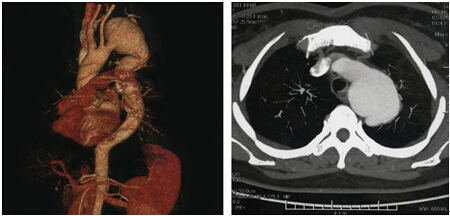

很明显,这是个巨大胸主动脉瘤合并主动脉夹层的患者,动脉瘤随时有破裂风险,意味着患者一只脚已经踏入了鬼门关。情况紧急,患者立即被转入心内科重症监护室,并在最短时间内用药物迅速控制了患者的胸痛症状,血压和心率也趋于稳定,病情暂时稳定。

不幸的是,该患者在胸主动脉瘤基础上,又同时合并主动脉夹层(也是主动脉最为凶险的疾病),病情就更为凶险了,死亡率极高。

在肖纯副院长指导下,由钟思干主任、廖火城和刘建平医生为核心的大血管团队经过详细的论证,最终决定为该患者实施支架植入的介入治疗。历时70余分钟,以廖火城医生为核心的大血管团队以精湛的技术为患者实施了胸主动脉腔内覆膜支架植入术,主动脉瘤合并夹层同时成功隔绝,且无大动脉内外瘘、截瘫、脑梗塞、消化道出血等并发症发生,患者体内“定时炸弹”被成功拆除!